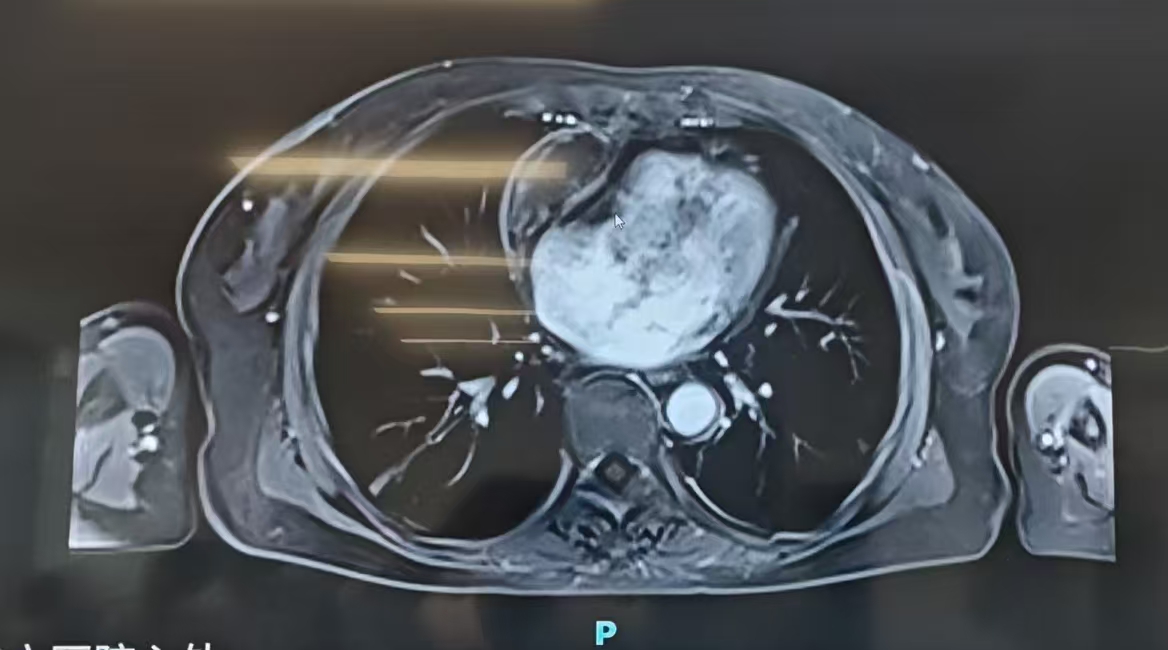

直到最终检查,才终于揪出幕后元凶:心脏前方隐匿着一颗直径约 8 厘米的心包内占位。

该病症临床发病率极低,症状极度隐匿,仅以腹水为首要表现,极易与消化、肝肾疾病混淆,误诊率极高。加之肿瘤位置特殊,紧邻心脏和大血管及神经,手术及术后风险极高。

接诊后,乔军选主任、何伦德主任医师及李正国教授团队第一时间联合多学科精细评估,明确诊断:肿瘤压迫右心室导致心功能受损,体循环淤血,进而引发顽固性腹水。患者合并冠脉支架术后、心功能不全等多种基础病,手术是唯一的根治途径。

术中探查发现,心包与心外膜粘连致密,合并缩窄性心包炎,肿瘤约 8×4×3 cm,剥离难度远超预期。手术团队凭借丰富经验,小心翼翼分离粘连,完整切除肿瘤。针对最关键的致命风险,团队采取「主动减负」策略:术中快速利尿约 2000 ml,术后转入 ICU 数小时内再次利尿近 2000 ml,有效减轻心脏负荷,成功规避急性心衰,最终无需启用 ECMO 等高级生命支持,平稳渡过危险期。整场手术历时 4 小时 7 分钟,出血仅 150 ml,病理显示肿瘤为良性。